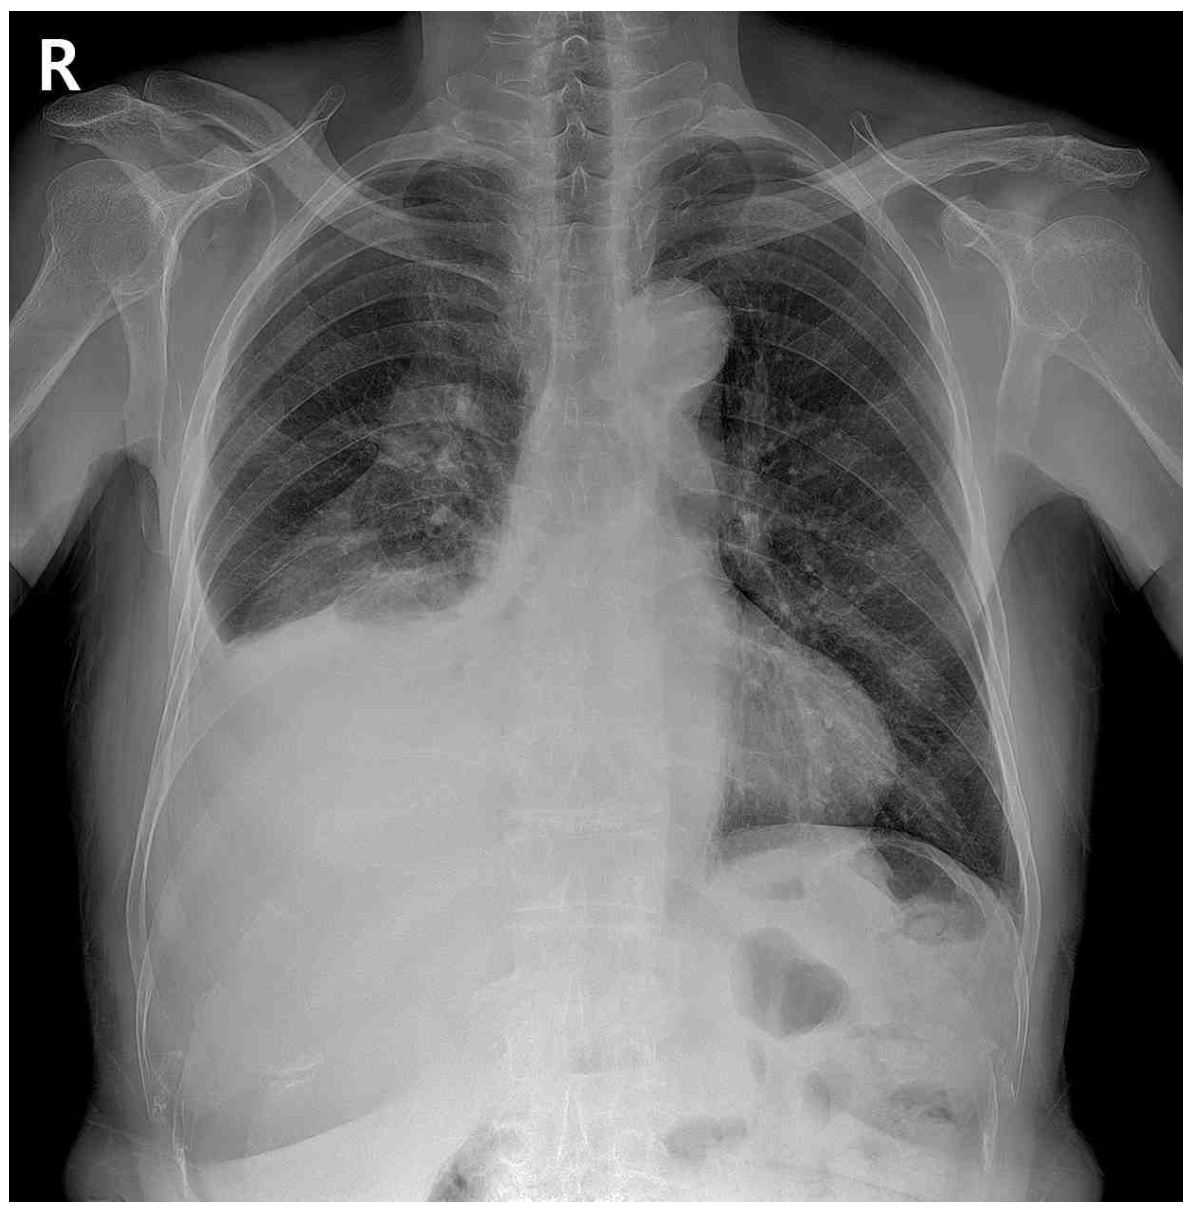

CXR: Rt. pleural effusion

• 수개월 전에는 호흡곤란의 정도가 mMRC 1 정도였으나 7일 전부터는 mMRC 2~3 정도로 악화한 것으로 보아 증상이 수개월 내 진행되고 있으며, 우측 가슴에서 호흡음이 감소되어 들리므로 해당 부위에 발생한 흉수, 기흉 등의 원인을 생각해볼 수 있다.

• CXR상 RLL diffuse opacity가 확인되며, 자세한 평가를 위해 실시한 Chest CT에서 거대한 mass와 Rt. pleural effusion이 관찰된다. Mass는 solid한 양상으로 irregular margin을 보이고 있으며 central necrosis가 의심되는 irregular enhancement의 소견이 관찰되는 바 폐암의 가능성이 높다고 판단할 수 있다.